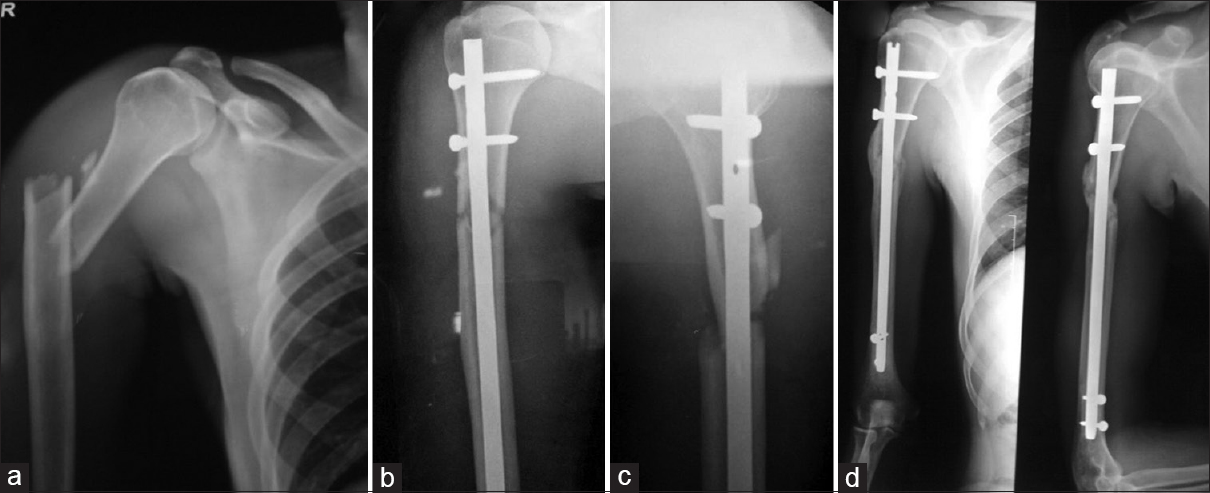

Un clou intramédullaire huméral est un dispositif médical conçu pour stabiliser et favoriser la cicatrisation des fractures de la diaphyse humérale.Il se compose d'une longue tige métallique qui est insérée dans le centre creux de l'os, offrant stabilité et soutien pendant le processus de guérison.Le clou est généralement en titane ou en acier inoxydable et est disponible en différentes tailles pour s'adapter aux différentes anatomies des patients.

Après avoir créé un point d'entrée, le chirurgien insère le clou intramédullaire de l'humérus dans le canal huméral.Un guidage fluoroscopique est utilisé pour assurer un placement et un alignement précis.L'ongle est avancé à travers l'os, réalignant tous les fragments déplacés et restaurant l'anatomie appropriée

Une fois le clou correctement positionné, des vis de verrouillage sont insérées pour fixer le clou dans l'os.Ces vis offrent une stabilité supplémentaire et empêchent les mouvements de rotation ou axiaux des fragments de fracture.Le nombre et le placement des vis dépendent du type de fracture et de la préférence du chirurgien.

De nombreux patients ont connu des résultats positifs avec la chirurgie des clous intramédullaires de l'humérus.Une étude de cas a impliqué une personne de 45 ans avec une fracture déplacée de la diaphyse humérale.Après avoir subi une intervention chirurgicale avec un clou intramédullaire, le patient a obtenu un excellent alignement de la fracture, a retrouvé une amplitude de mouvement complète et est revenu à son niveau d'activité d'avant la blessure dans les six mois.